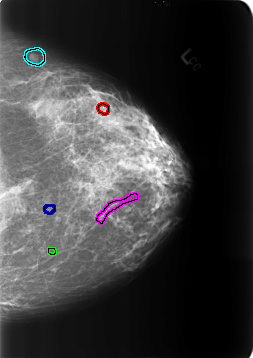

B_3240_1.RIGHT_MLO

FILE: B_3240_1.RIGHT_MLO.OVERLAY

TOTAL_ABNORMALITIES 3

ABNORMALITY 1

LESION_TYPE CALCIFICATION TYPE ROUND_AND_REGULAR-LUCENT_CENTER DISTRIBUTION N/A

ASSESSMENT 2

SUBTLETY 4

PATHOLOGY BENIGN_WITHOUT_CALLBACK

ABNORMALITY 2

ABNORMALITY 3

LESION_TYPE CALCIFICATION TYPE VASCULAR DISTRIBUTION N/A